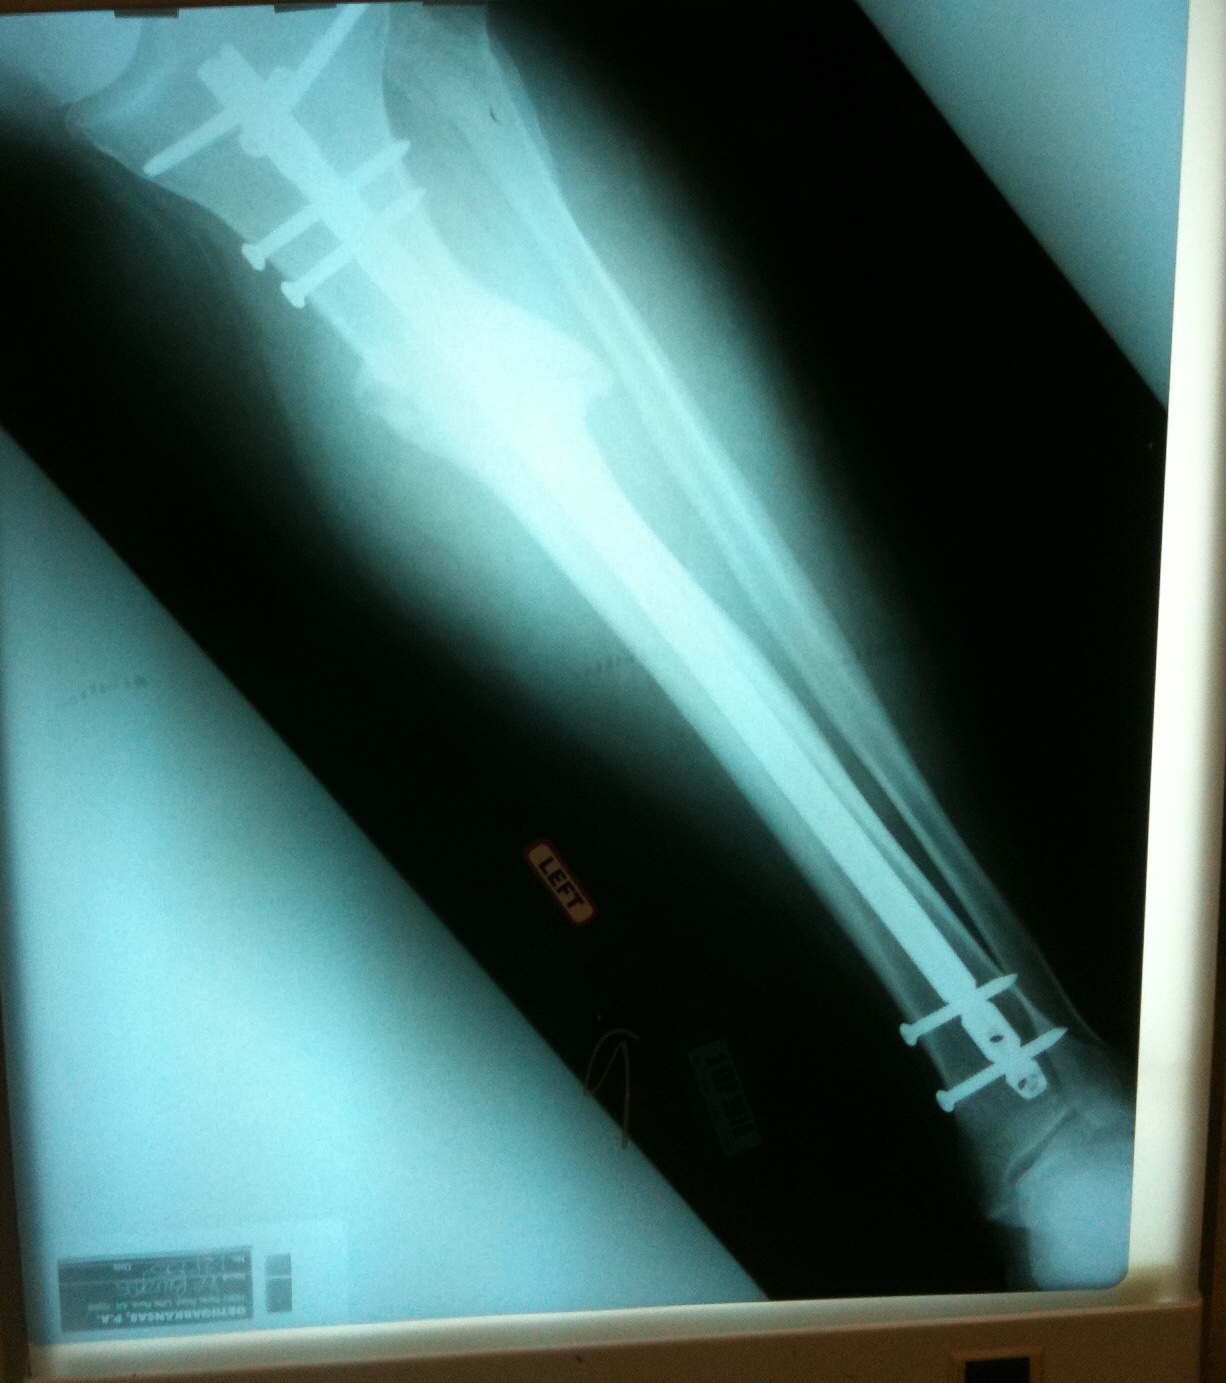

Burgess received treatment at Drew Memorial Hospital, then was transported to Baptist Medical Center in Little Rock for surgery to repair a broken tiba and fibula in his left leg.